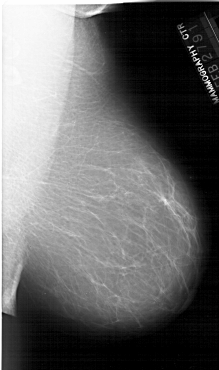

A_1916_1.LEFT_MLO

LEFT_MLO LINES 5956 PIXELS_PER_LINE 3721 BITS_PER_PIXEL 12 RESOLUTION 43.5 OVERLAY